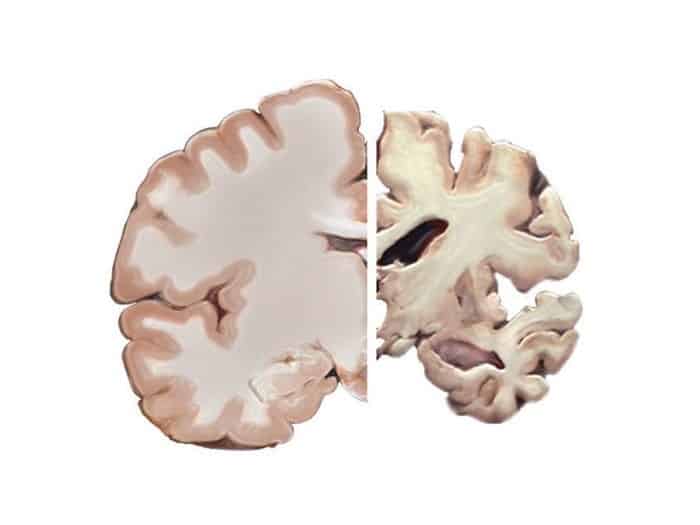

وتمثل الدراسة مثالا على السعي من قبل العلماء لمكافحة مرض الزهايمر الذي وإلى الآن لايوجد له علاج جذري بالإضافة لقلة الفحوصات اللي يمكن الاعتماد عليها لتشخيص المرض. ويعتبر مرض الزهايمر في الولايات المتحدة وباء صحي يؤثر على أكثر من 5 ملايين أمريكي. ولذا يسعى الباحثون إلى تطوير مؤشرات حيوية يمكن الاعتماد عليها لتشخيص المرض في مراحله الأولى قبل حدوث تلف في المخ، وحدوث الخرف.